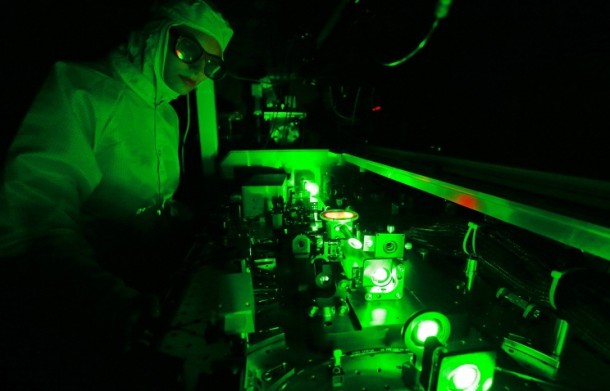

Олимони рус, тасвири организми инсонро дар компютер ҷойгир карданд

Коршиносони рус, ки барои пешрафти соҳаи тиб саъю талош меварзанд, тавонистанд сохти организми инсон ва кори узвҳои дохилии онро бо ... -